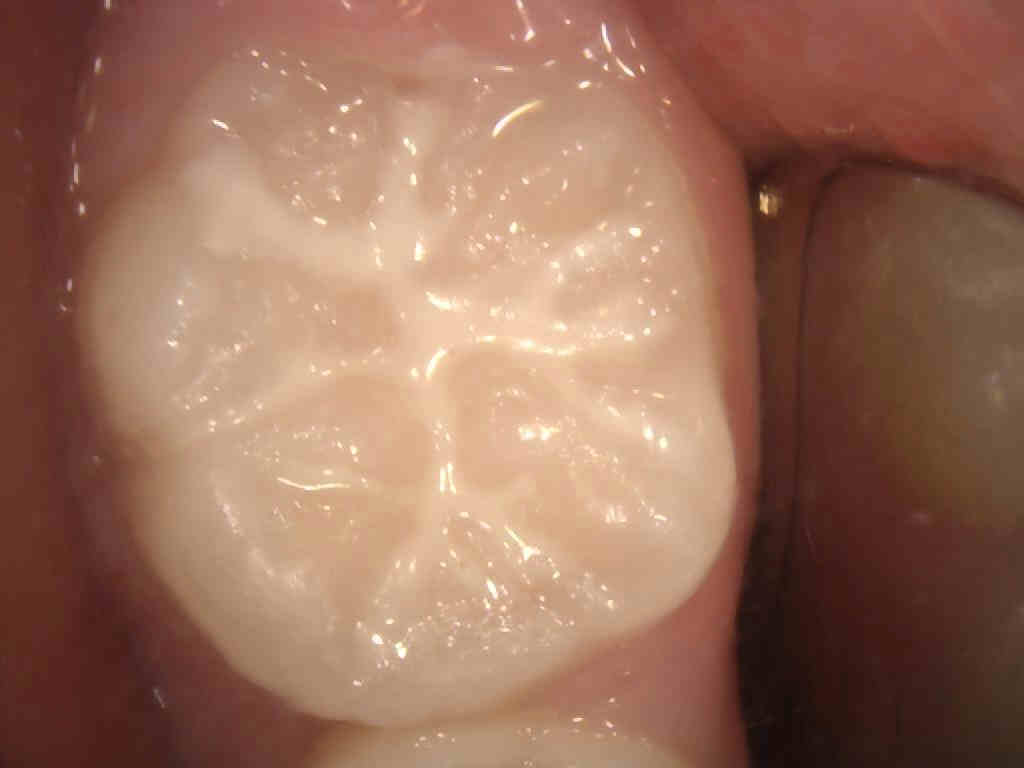

乳歯や永久歯の噛み合わせの面にある溝をプラスチックの材料で埋めて、虫歯になりやすい深い溝伸の部分を塞ぐ処置です。

そして、咬み合う面は複雑な形態で溝が深いため、特に磨きにくいのでブラッシングが難しく汚れが溜まりやすいこともあり、虫歯になるリスクが高くなります。特に6歳頃に奥歯に生えてくる永久歯はとても虫歯になりやすい歯です。